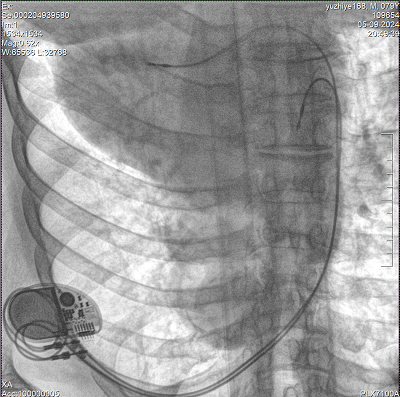

具備血管造影及數(shù)字減影(DSA)、路徑圖(Road-map)、透視、攝影等功能。 廣泛適用于介入科、血管外科、腫瘤科、消化內科及骨科等多個臨床科室,典型應用包括:TACE(肝腫瘤栓塞與化療灌注術)、心臟起搏器置入術、四肢動脈造影術、下肢靜脈濾器置入術、ERCP(經內鏡逆行胰膽管造影術)等。

設備搭載自主研發(fā)的大功率高壓發(fā)生器、高熱容球管與大尺寸平板探測器,配合先進圖像處理算法及高效冷卻循環(huán)系統(tǒng),能夠在長時間手術過程中持續(xù)輸出高清圖像并保持幀率穩(wěn)定。

預留高壓注射器聯(lián)動接口,C形臂開始透視時,高壓注射器自動注入造影劑,提高術中造影減影效率,減少醫(yī)師手推造影劑所受到的輻射暴露劑量。

通過床旁控制器,可以完成設備的運動控制、曝光參數(shù)調節(jié)、圖像的瀏覽和保存等常規(guī)操作。